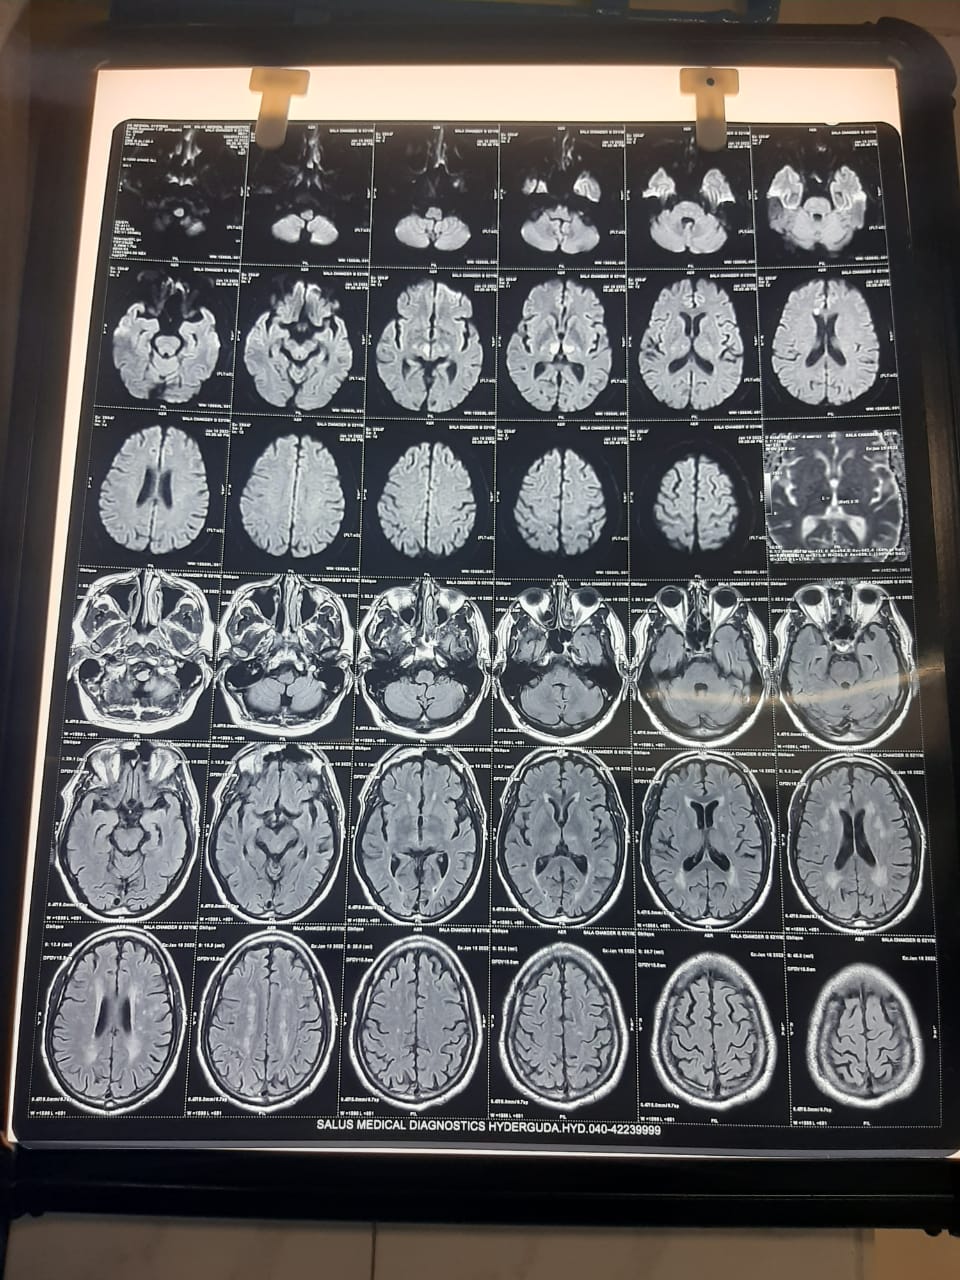

WEEK 5 :ANTERIOR CHOROIDAL ARTERY INFARCT